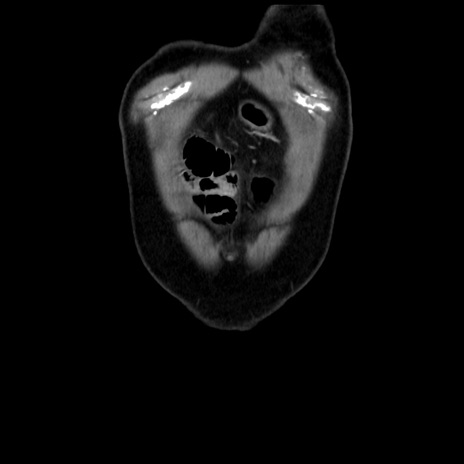

横断像